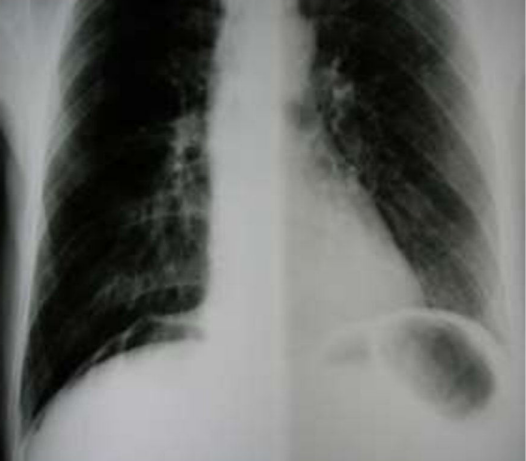

Homem, 61 anos. Admitido na emergência após dor abdominal de início súbito e de forte intensidade há 3 h. Fumante. Ao exame: taquicárdico, estável, abdome em tábua. Rx tórax abaixo. Achado cirúrgico: úlcera gástrica ( 1,5cm) perfurada pré-pilórica. Realizada biópsia das bordas da úlcera e ráfia primária com omentoplastia.

Sobre esse caso, assinale a alternativa CORRETA.